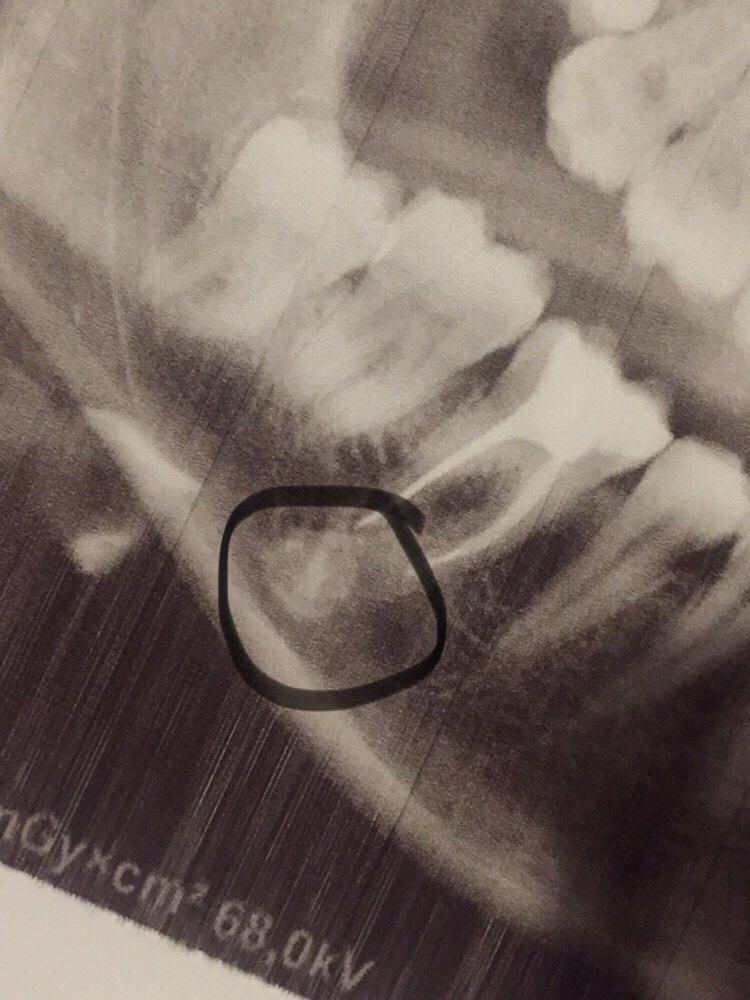

Одонтома нижней челюсти: фотографии и медицинская информация

Раздел: Фотобанк решений